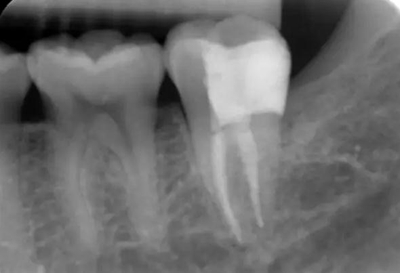

圖11 術后X線片:37恰填,遠中鄰面樹脂充填物密合,無懸突。